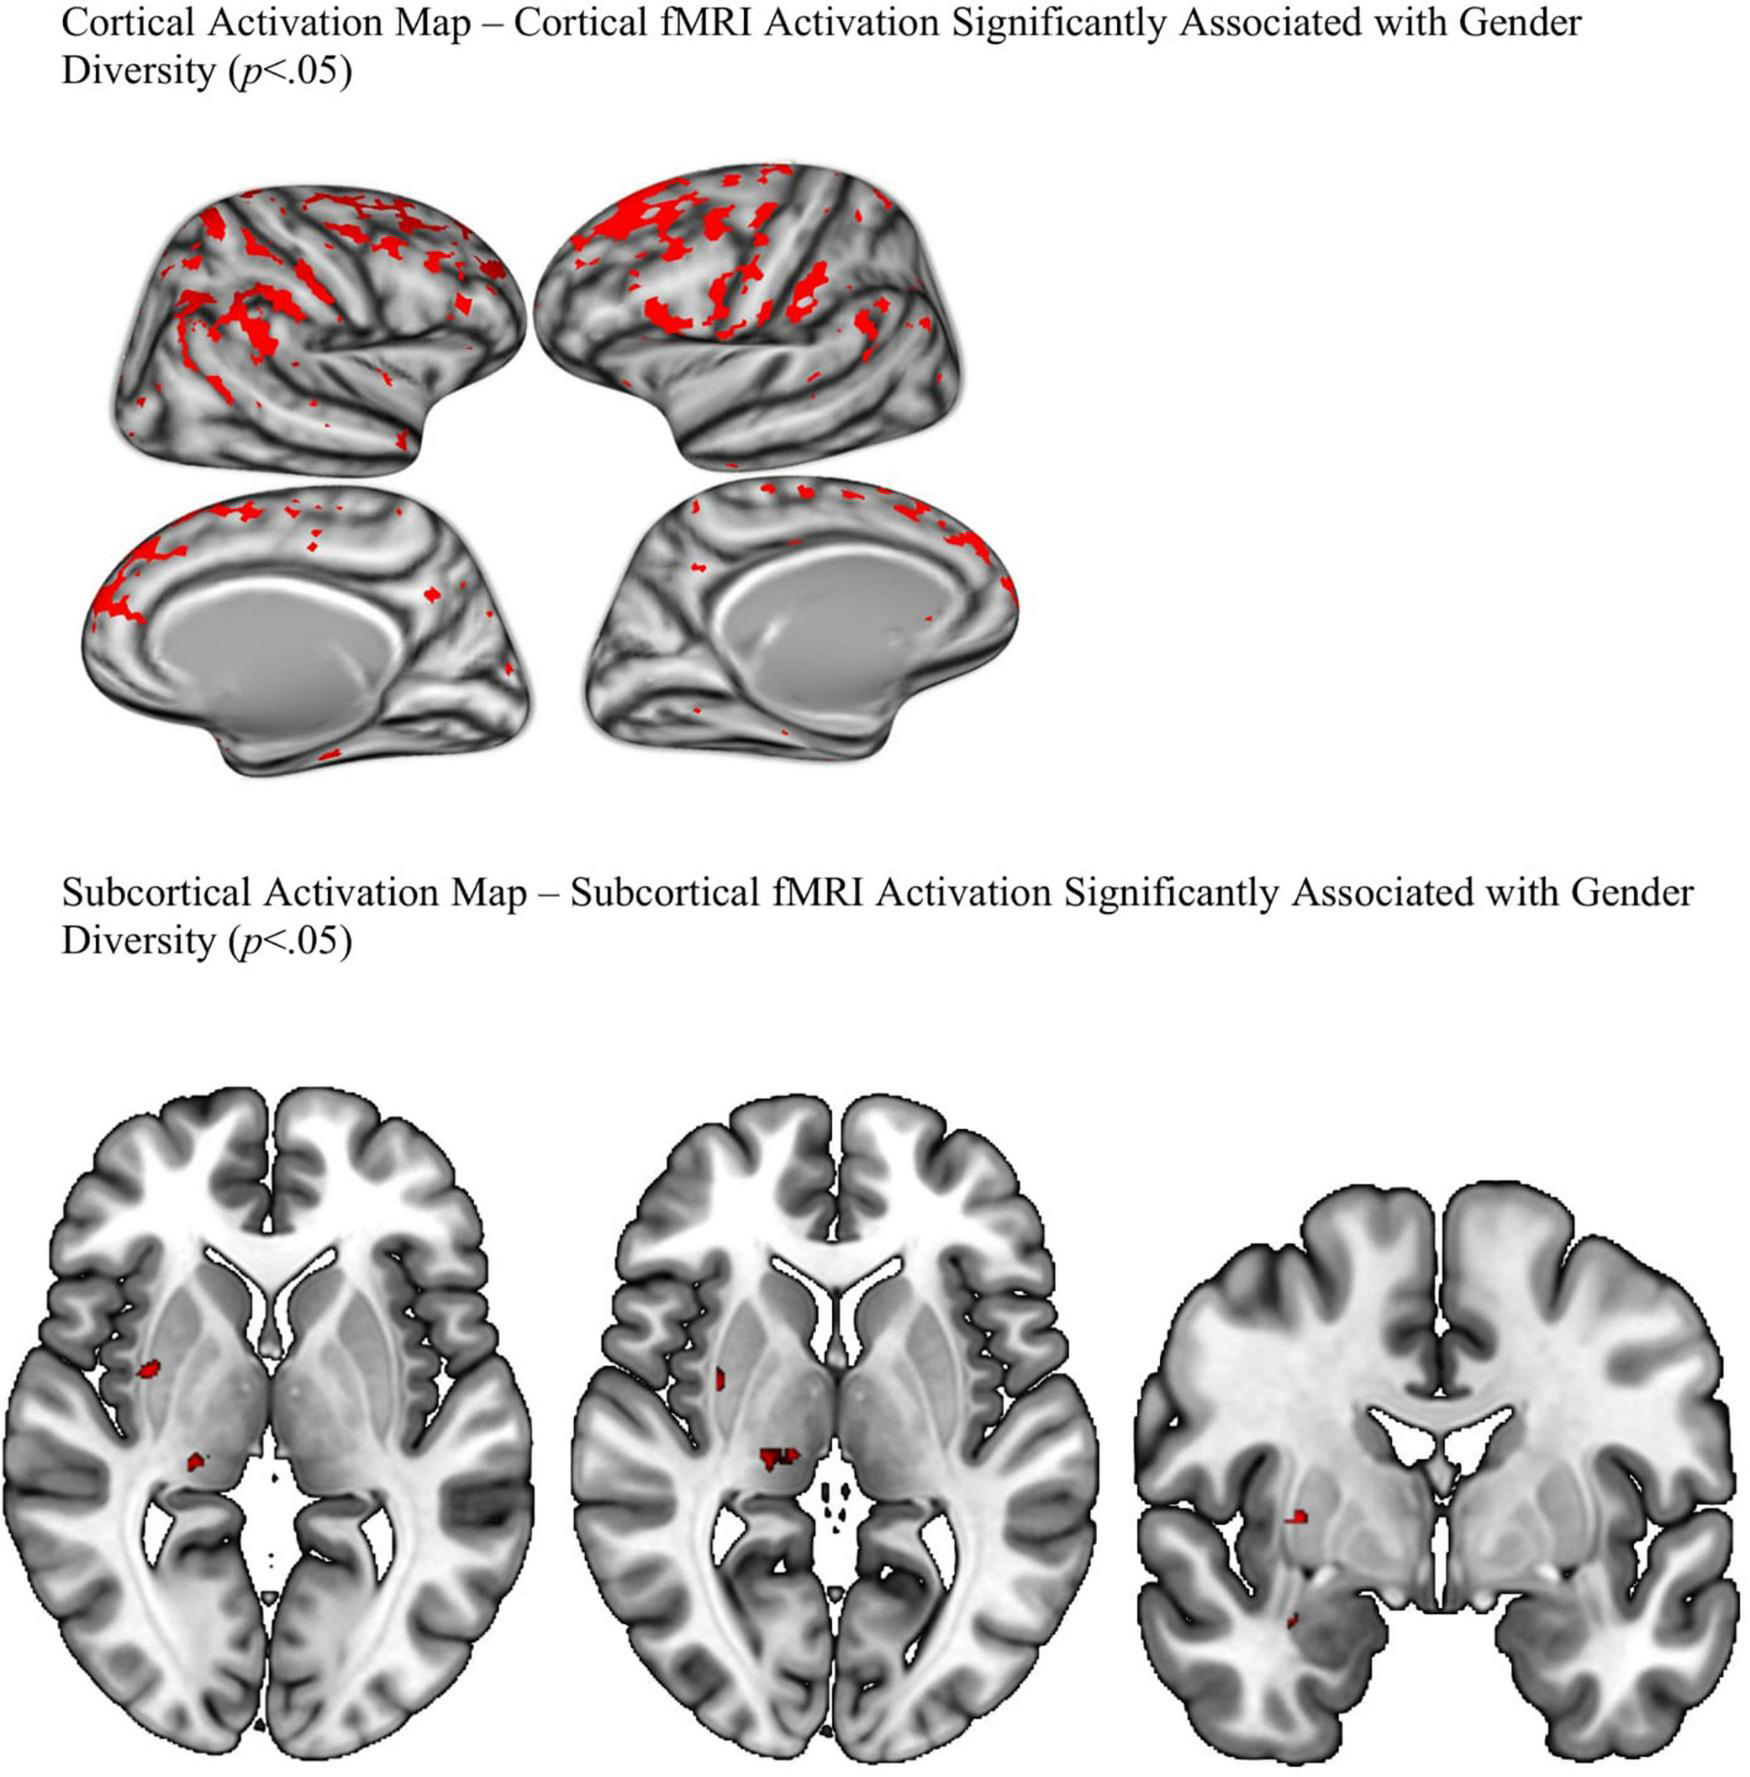

Cortical and subcortical p-value maps were generated to model activation patterns of recoded gender diversity on emotional faces (activation when viewing faces—neutral, happy, and fearful, minus activation when viewing places, collapsed across working memory load) and are displayed in Figure 4. On the cortical map, gender diversity was associated with wide-spread greater bilateral activation in task-related areas. Specifically, the fusiform, orbitofrontal (lateral and medial) areas, rostral middle frontal region, occipital and parietal regions. Consistent with our hypothesis, the cortical map showed greater activation of bilateral insula, superior temporal gyrus, and parahippocampal gyrus with more gender diversity when viewing emotional faces compared to places (p < 0.05, FDR-corrected). The subcortical map suggested gender diversity associated with right amygdala, as predicted by the stress literature, as well as activation in the right putamen. No differential activation was detected in the dorsal anterior cingulate cortex in either map.

FIGURE 4

FDR corrected P-value maps.

The current study found that greater gender diversity in a community sample of youth is associated with increased BOLD signal in task-related brain regions. Specifically, the fusiform, orbitofrontal (lateral and medial) areas, rostral middle frontal region, occipital and parietal regions known to be active during recognition, visual/sensory perception, emotion, and memory. Consistent with our hypothesis, gender diversity was also associated with areas commonly activated in populations that experience stress such as the superior temporal gyrus (e.g., De Bellis et al., 2002; Hein and Monk, 2017), parahippocampal gyrus, amygdala and insula (e.g., Hein and Monk, 2017). Inconsistent with our hypothesis, gender diversity was not associated with activation in the dorsal anterior cingulate cortex. This may suggest that the dorsal anterior cingulate cortex is not associated with stress related to gender diversity. An additional reason we may not have found significant findings in the dorsal anterior cingulate is because gender diversity and fMRI imaging data were collected at different time points. The effect may have been stronger had gender diversity and brain imaging been collected at the same time. Our results support our hypothesis that gender diversity is associated with brain activation patterns that are consistent with other types of childhood stress (e.g., Etkin and Wager, 2007; Hein and Monk, 2017; Miller et al., 2020).